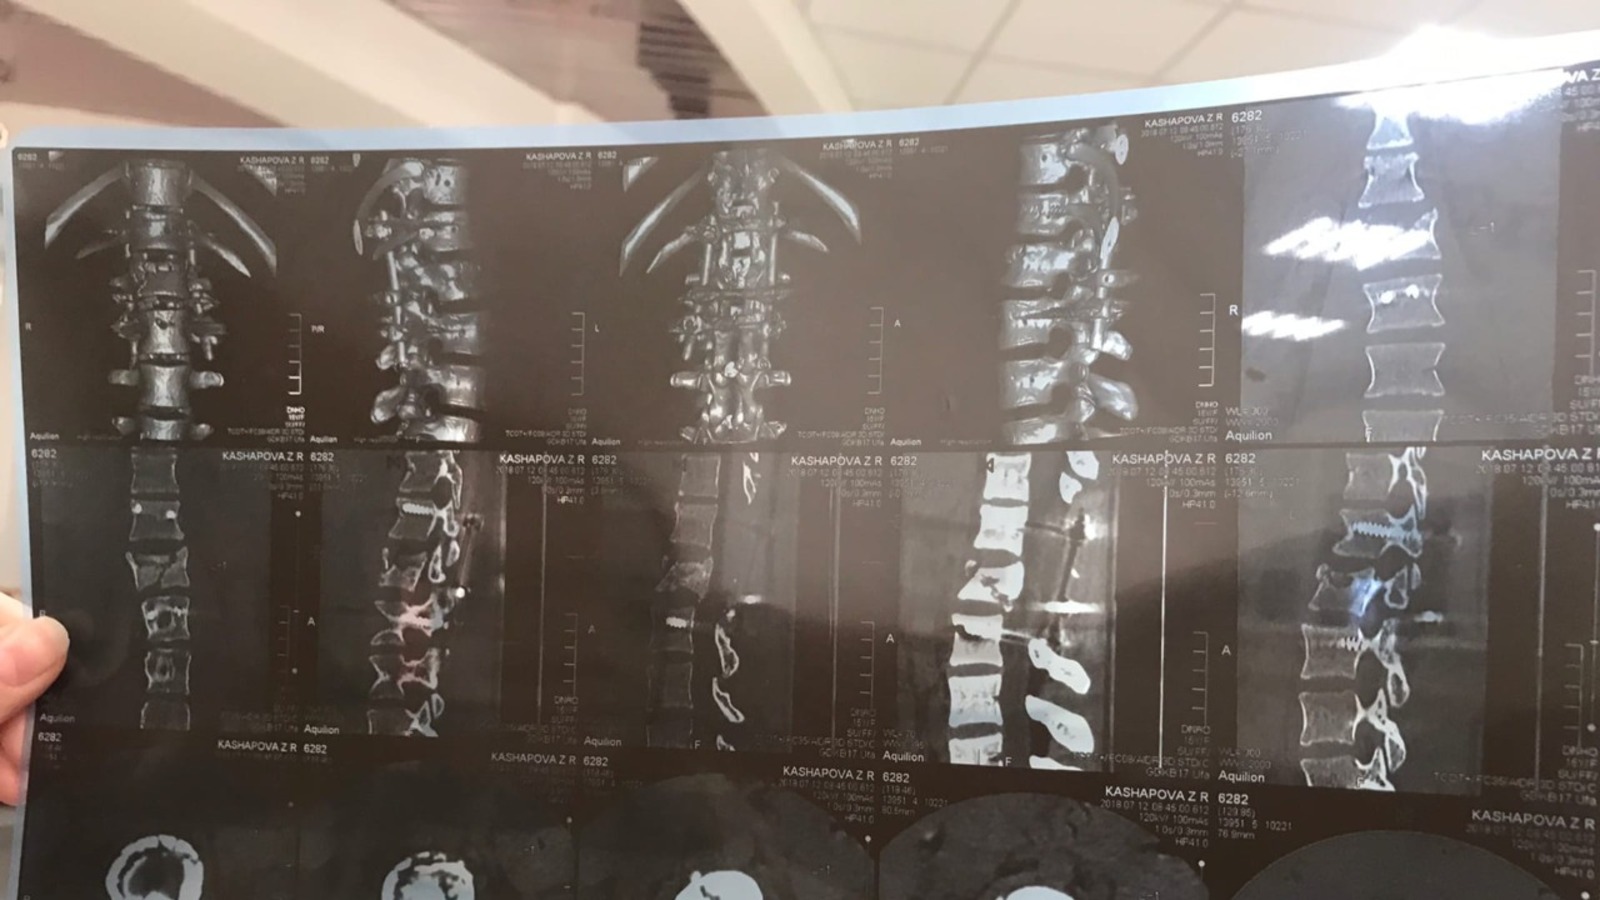

«В больнице сделали снимки, поместили пациентку в реанимацию, готовили к операции. Поставили капельницы на две руки, катетер. Родители приехали в больницу, но их не пускали. Мыслей о том, буду ли я ходить, или навсегда останусь прикованной к постели, не было. Я не понимала, насколько все серьезно. У меня спрашивают, что произошло, я объясняю. Полицейские приехали, стали допрашивать – я реву», - поделилась воспоминаниями Зульфира.

«В операции участвовала целая бригада. Врачи даже устали. Мне разрезали спину. Спинной мозг был со всех сторон зажат, как мне сказали, он мог вообще лопнуть, и я бы осталась парализованной на всю жизнь. Но они успели разжать и все сделать, чтобы я вновь могла встать на ноги, - сообщила героиня. – Где-то через день ко мне пришли врачи, сказав, что нужно простынь поменять. Они резко поставили меня на ноги, я стала дергаться, в глазах потемнело. А они снова меня положили: оказывается, так проверяли, могу ли я стоять на ногах, а про простынь – пошутили. Я устояла – это был хороший знак. По ощущениям, будто я впервые встала, словно маленький ребенок, который не умеет ходить. Через неделю после операции начала более-менее передвигаться. Делала лечебную гимнастику, переворачивалась с бока на бок – соблюдала все рекомендации. Мама была в палате со мной, кормила меня, помогала. Родители меня не обвиняли, не ругали, были рады, что жива осталась».

«Вторая операция прошла легко. Делали надрез сбоку, правда швы долго заживали. Были ограничения в еде, диета, - отметила она. – Школу пришлось заканчивать дистанционно – ОГЭ сдавала, находясь дома. Я поступила в Уфимский колледж ремесла и сервиса им. Ахмета Давлетова. А хотела поступить в колледж ландшафтного дизайна, куда-нибудь поинтереснее, посложнее. Но по медицинским показаниям, не получилось».

«Была зима, гололед – я несколько раз падала, но думала, что не сильно. На осмотре выяснилось, что я сломала два болта. Прошло мало времени, кости с конструкцией не срослись. Мне назначили операцию на март 2020 года, а тут этот коронавирус - операцию перенесли на июнь. Потом из-за какой-то реконструкции больницы снова перенос на 2 сентября. Все это время пришлось носить поддерживающий корсет», - рассказала собеседница.